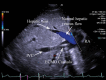

Introduction: Optimal positioning of double lumen bicaval canula for extracorporeal membrane oxygenation (ECMO) support used as a rescue measure in refractory hypoxaemia is essential to facilitate adequate oxygenation, prevent recirculation and avoid complications. Method: Echocardiography via transoesophageal or transthoracic windows can be used as guidance and as a surveillance technique to prevent cannula malposition. We describe a case of Double-Lumen Bicaval VV ECMO cannula malposition leading to a massive retrograde hepatic venous flow. Conclusion: Rapid echocardiographic diagnosis was pivotal in preventing potentially fatal complications.